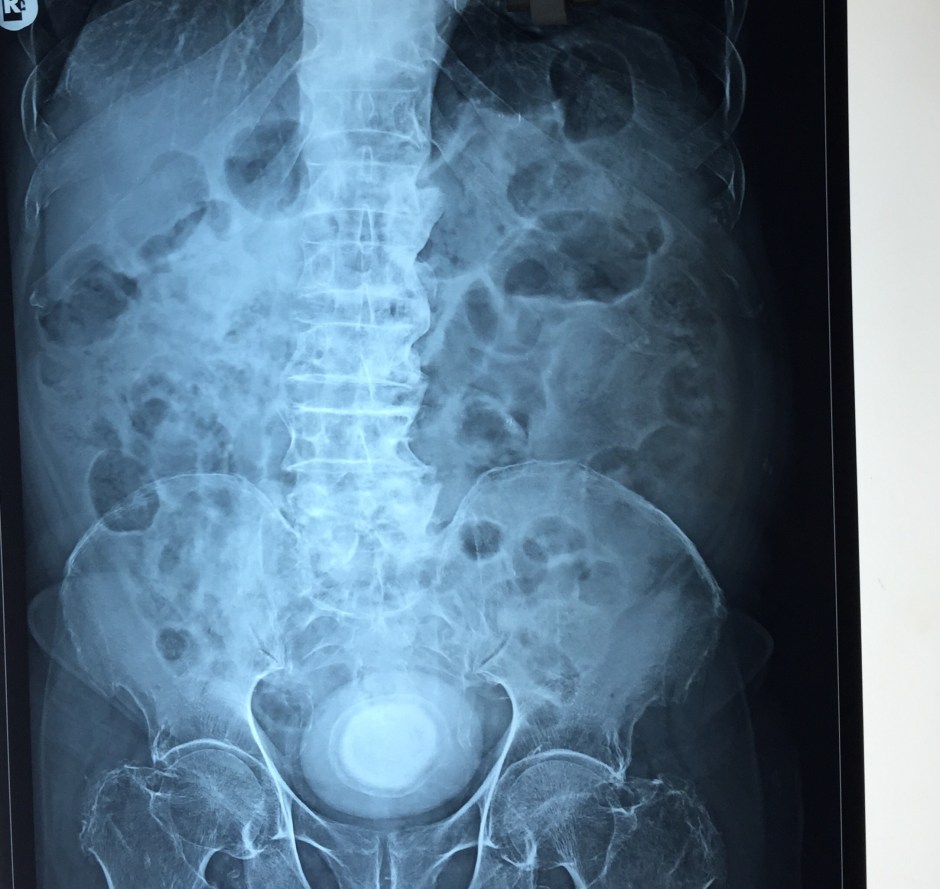

The X-ray and the CT scan pictures are given below.

A large calcification in the urinary bladder – ? large urinary bladder stone , calcified median lobe of the prostate, or a calcified mass within the bladder .

LARGE CALCULUS IN THE URINARY BLADDER WITH MULTIPLE DIVERTICULAE IN THE BLADDER “